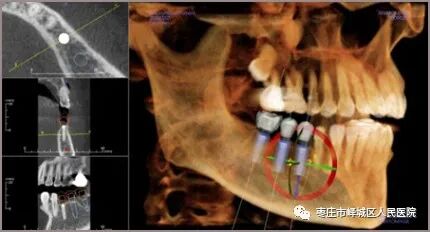

种植牙

‍‍利用口腔CT精准判断全口牙床的位置、牙槽骨的高度和深度等,医生可在计算机上清楚判读出牙槽骨的情况,重建成3D数字模型,在计算机上事前做好种植计划,选择适当的种植体,决定最佳的种植位置与角度,进而制造成精确的手术模板,让种植牙更加安全。口腔ct怎么看您知道吗?口腔也可以做“CT”哦~_https://www.jmylbn.com_新闻资讯_第11张